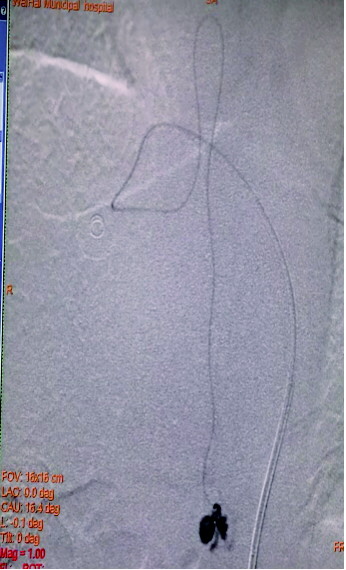

CTA结果很快出来,考虑为胸髓血管病变,动静脉畸形的可能性大,于是,王亮再次对患者行全脊髓造影,明确病变的性质。最终,造影显示病人病变为胸11的脊髓髓周瘘,由第9肋间动脉的脊髓前支供血,回流静脉明显增粗并形成一个大的“静脉球”,病例得到确诊。

图A为术前造影的正位图像,主供血为脊髓前动脉,引流静脉的起始部形成一个静脉球,远端呈迂曲状;图B为微导管到位后的超选造影,脊髓前动脉不显影(已越过);图C为栓塞结束后的造影,主供血的血流明显瘀滞,瘘口闭塞,下方的脊髓前动脉仍显影。